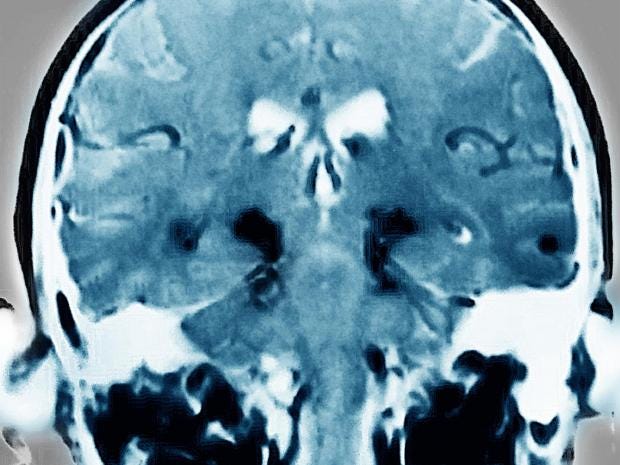

The researchers believe that DJ-1 plays a role in preventing the build-up of defective molecules which form harmful protein clumps, known as Lewy bodies, in the brains of Parkinson's patients.

Symptoms are caused by the death of nerve cells in a part of the brain linked with the production of the neurotransmitter chemical dopamine, which is vital for human movement.